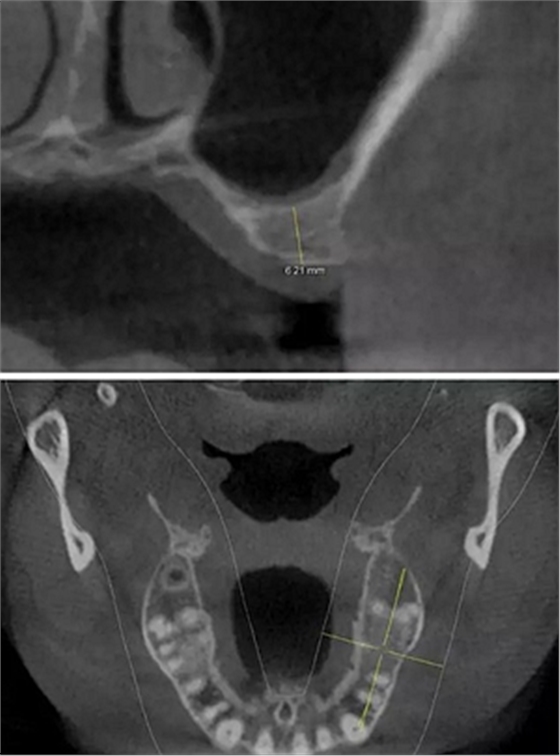

術(shù)后CBCT

提升時(shí)相關(guān)步驟可參考下面圖片

可見在完善的檢查和適當(dāng)?shù)墓ぞ哌x擇下可順利完成較復(fù)雜的上頜竇手術(shù)。